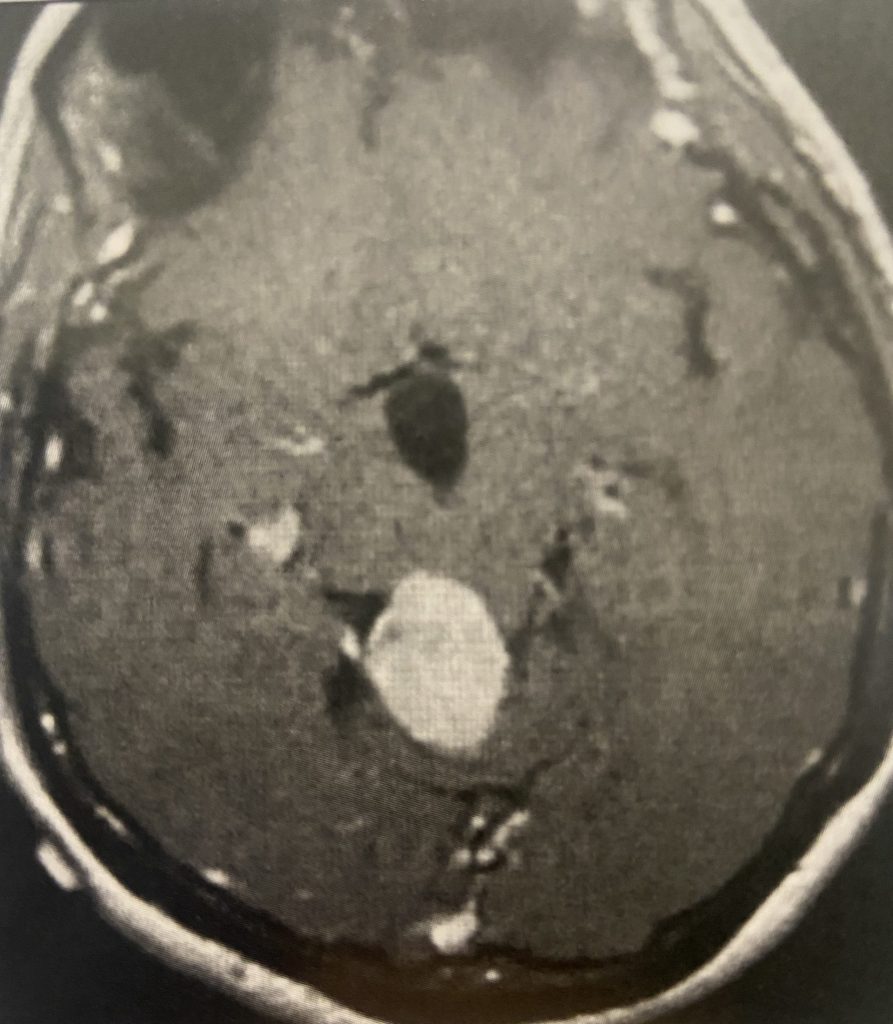

Figure 4

Postoperative post contrast axial MRIs demonstrating complete removal of the tumor with resolution of the hydrocephalus.

Subsequently, the hydrocephalus resolved and the patient did not require shunting. Her pre-operative symptoms all resolved. Follow up MRI demonstrated complete removal of the tumor.